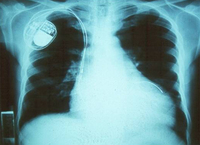

Chest x-ray: cardiomyopathy, heart enlargement

Grupo de Estudo em Correlalacao Anatomo-Clinica, Clínica Médica, Pontificia Universidade Catolica de Campinas, Sao Paulo, Brazil; used with permission